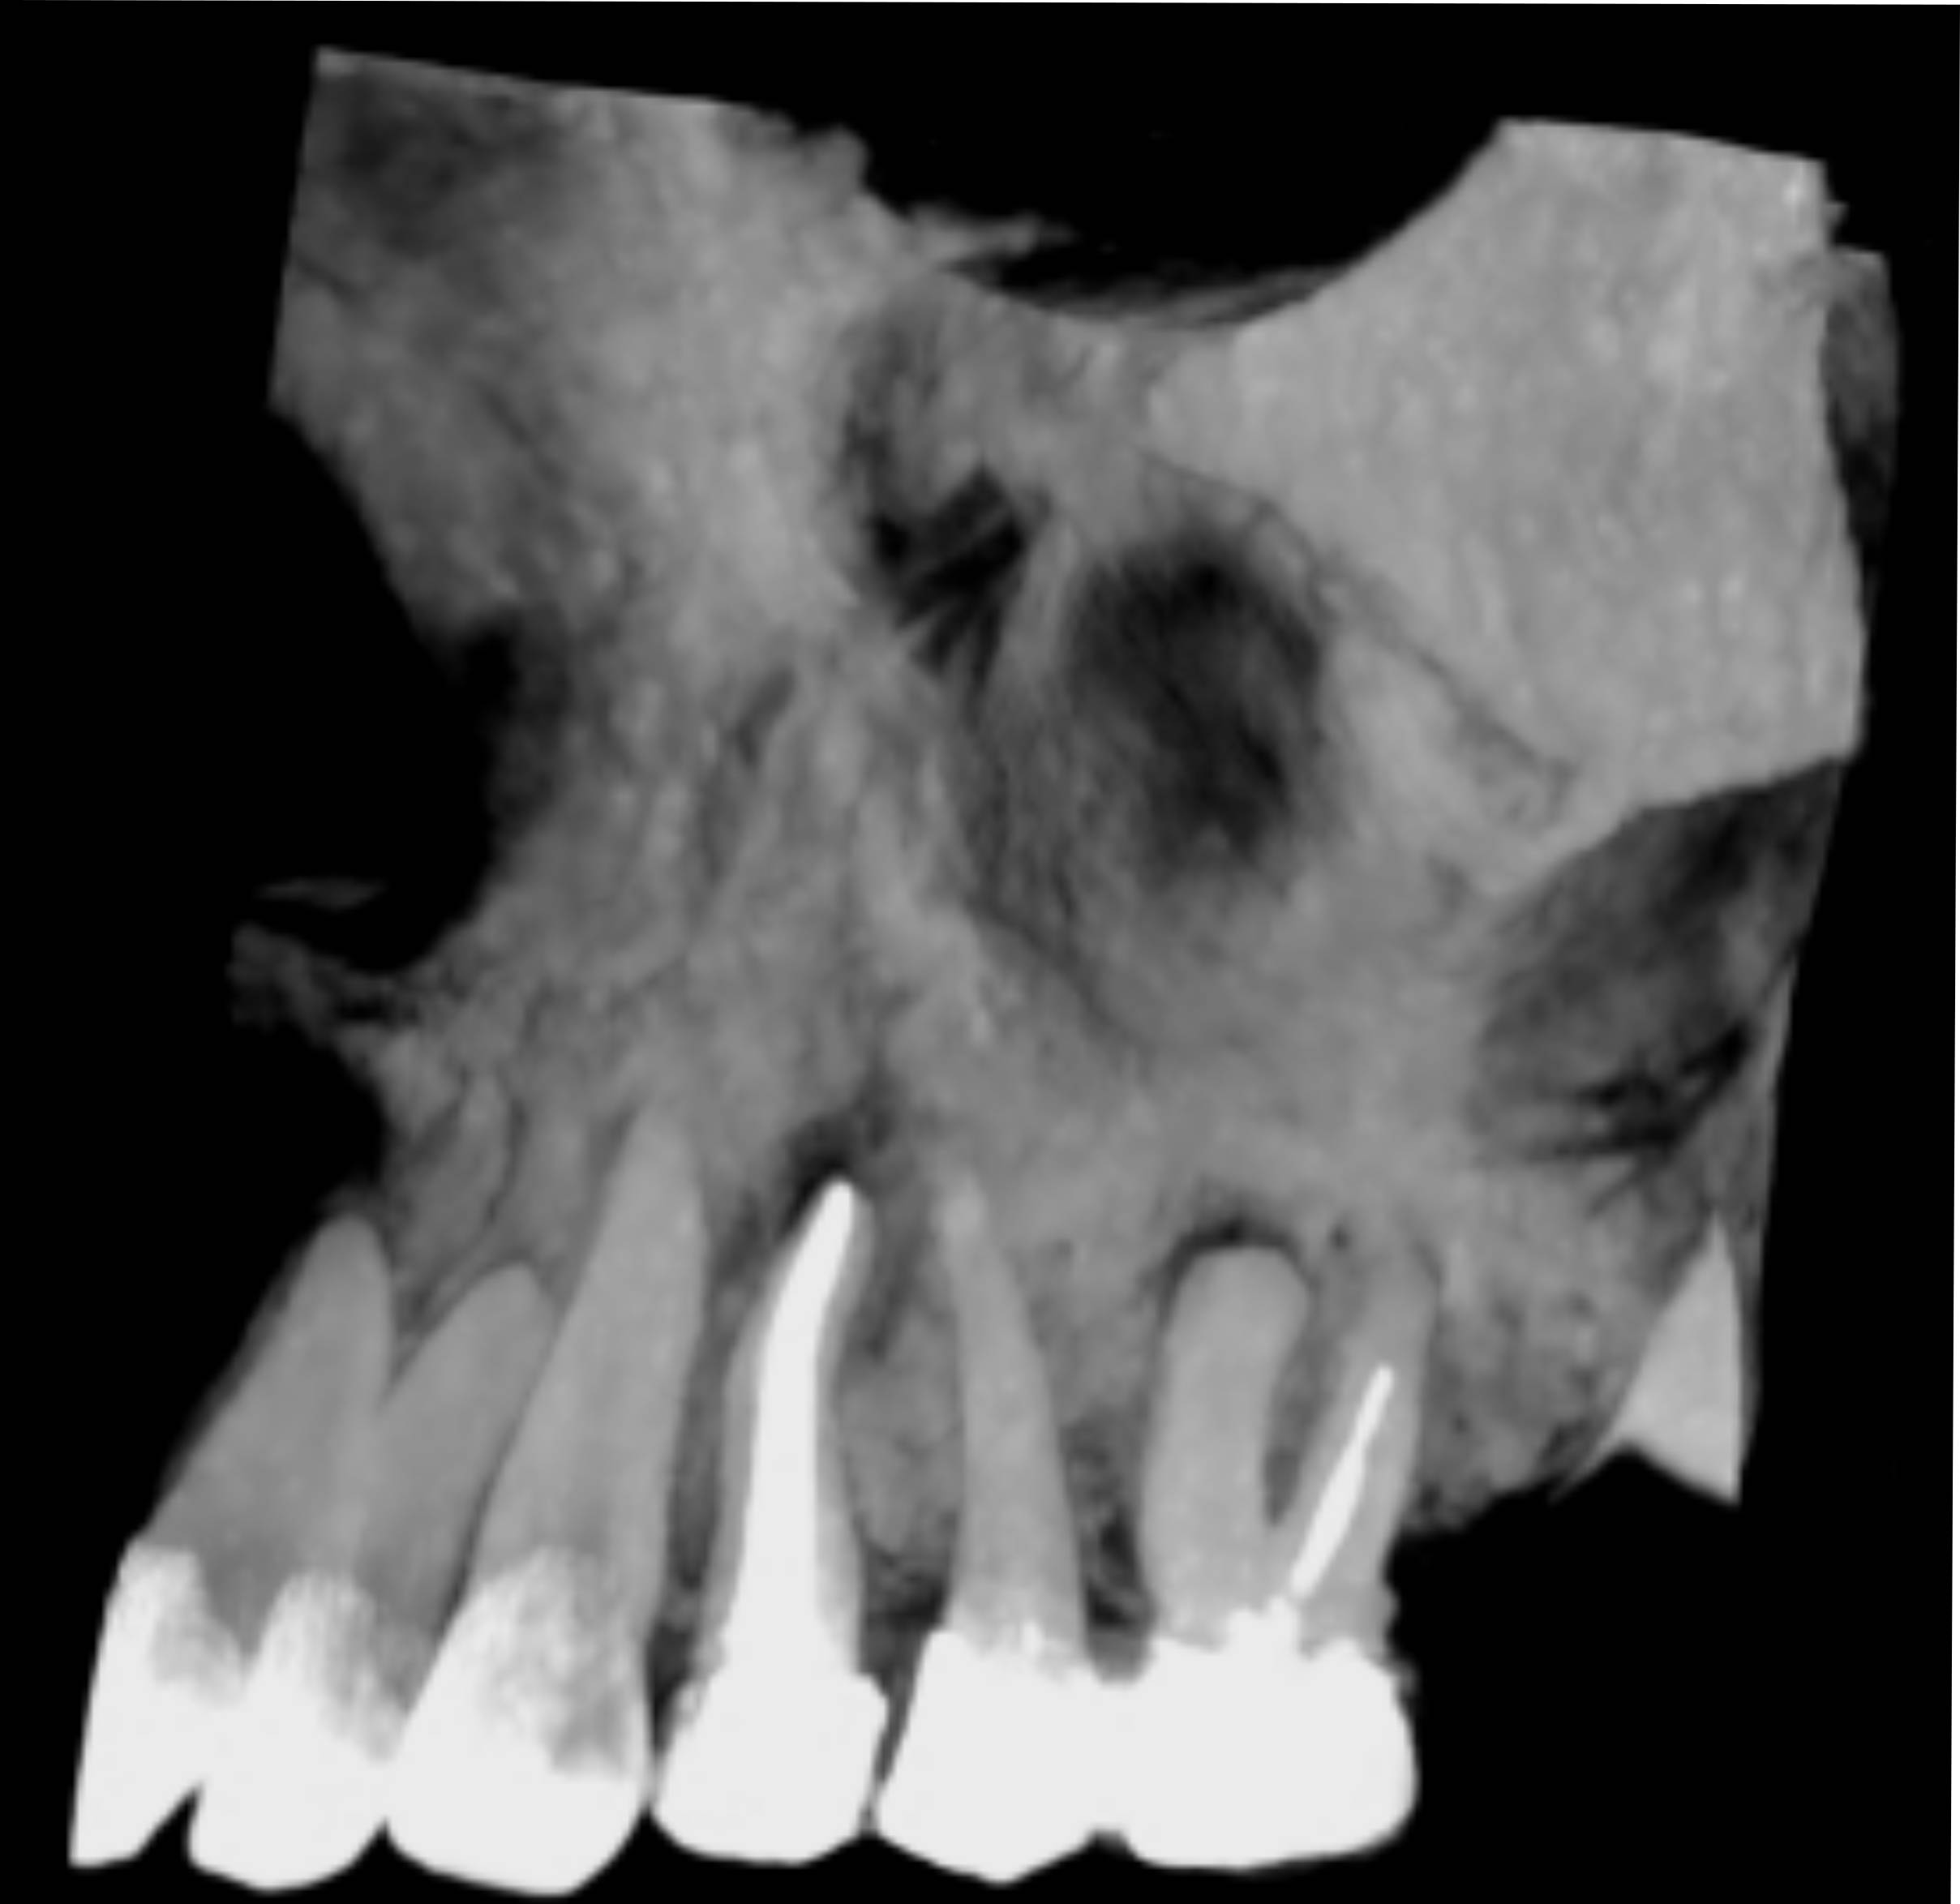

< Volver a "Diagnóstico por Imagen Dental"El examen CBCT es extraordinariamente útil tanto para endodoncistas como para periodoncistas, dado que ofrece imágenes de altísima calidad que permiten identificar todos los detalles de la zona a estudiar, determinar con exactitud la patología y planificar meticulosamente un tratamiento eficaz, así como la antamoía y sus posibles variantes

Resulta especialmente indicado para la evaluación de lesiones apicales, planificación en tratamiento de dientes fracturados o fisurado, lesiones en la cámara pulpar y de los conductos radiculares, tanto en número como en relleno de material de obturación.Los distintos tamaños de FOV permiten reducir la exposición a la radiación del paciente, limitándola a la zona de interés.